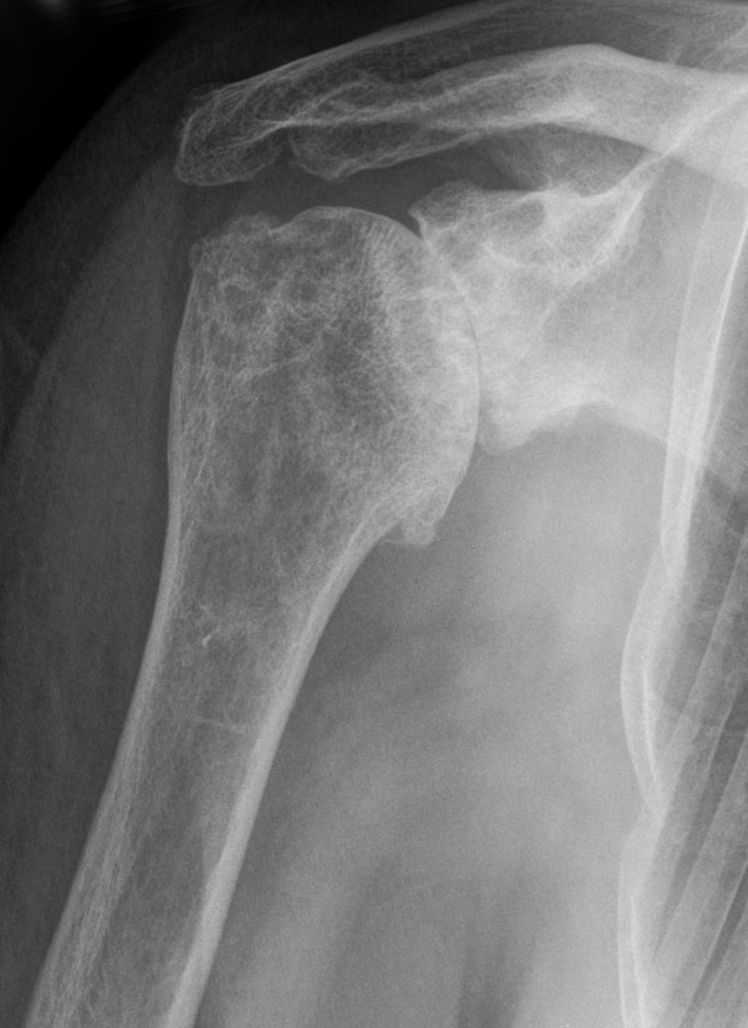

Radio d'arthrose de l'épaule

Cette usure du cartilage s’accompagne également de modifications et d’une déformation de l’os situé sous le cartilage, aussi bien au niveau de l’omoplate que de l’humérus.

Cette arthrose entraîne alors des douleurs et une diminution de la mobilité de l’épaule, s’aggravant progressivement. Ainsi, il est de plus en plus difficile d’utiliser le bras, que ce soit dans les gestes de la vie quotidienne, de la vie professionnelle ou dans le cadre d’une pratique sportive.